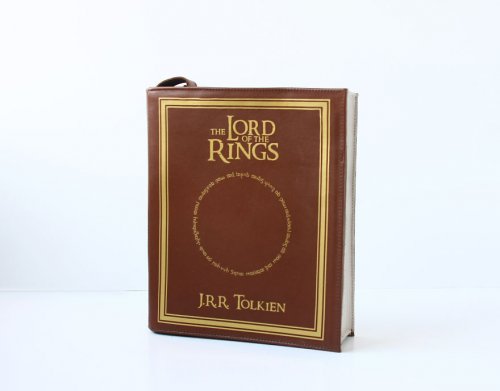

1. Простата в форме сердца

Предстательные железы есть только у мужчин и ответственны за питание и защиту спермы. Обычно предстательная железа обладает формой грецкого ореха, но эта предстательная железа необычной формы была обнаружена во время обычного осмотра у одного мужчины, являющегося пациентом врача Никхила Бансала (Nikhil Bansal) в больнице в Джайпуре (Jaipur), Индия. Предстательные железы в форме сердца являются большой редкостью. В то время как они выглядят забавно, они не представляют собой никакого риска для здоровья мужчины. На этой фотографии изображён снимок ультразвука простаты.